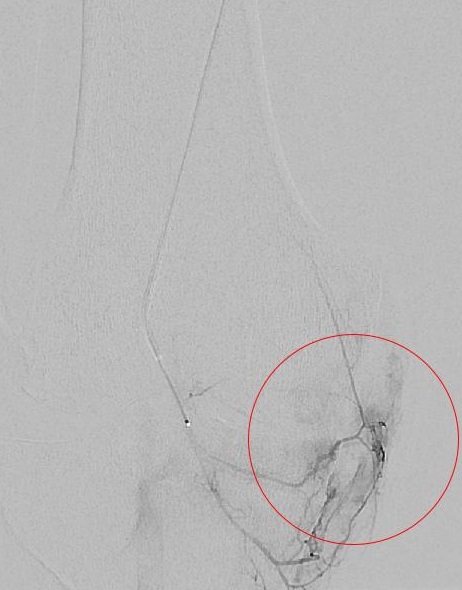

Um diesen Kreislauf zu unterbrechen kann die Blutzufuhr auf Höhe des Gelenkes durch das innovative Verfahren der Gelenkarterienembolisation reduziert werden. Hierbei wird in lokaler Betäubung die Leisten- oder Armarterie punktiert und ein dünner Kunststoffschlauch (Mikrokatheter) bis in die kleinen Arterien des entsprechenden Gelenkes eingebracht. Durch permanente oder temporäre Mikropartikel, welche in das Gefäßsystem eingebracht werden, kann die krankhafte Blutzufuhr des Gelenkes unterbunden werden (untere Bildreihe).

Somit wird die Entzündungsreaktion und die Überempfindlichkeit der krankhaften Nervenenden vermindert. Die Folge ist eine deutliche Schmerzlinderung im betroffenen Gelenk, meist schon in den ersten Tagen nach dem Eingriff. Nach Studien liegt die Erfolgsrate bei der am häufigsten angewendeten Kniegelenksembolisation 4 Jahre nach dem Eingriff bei 80 Prozent.